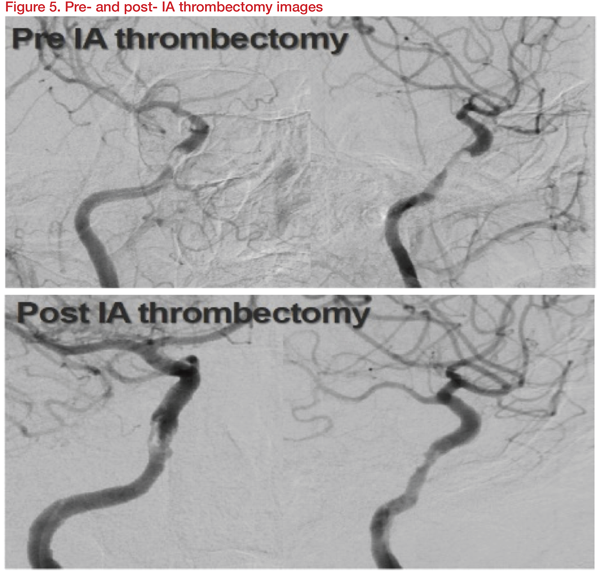

An 80-year-old presented with left hemiparesis and dysarthria and NIH stroke scale (NIHSS) of 7. She was diagnosed with an acute infarction involving right basal ganglia and frontoparietal area and severe stenosis involving right distal ICA, probable cavernous segment. The patient was treated with dual antiplatelet/high dose statin. Six days later, the symptoms worsened with altered mentality. The NIHSS score deteriorated from 7 to 14. IA thrombectomy using Trevo stent was performed. Though the residual stenosis remained, the right cavernous ICA was recanalized, and the patient improved to 7 NIHSS points (Figure 5).